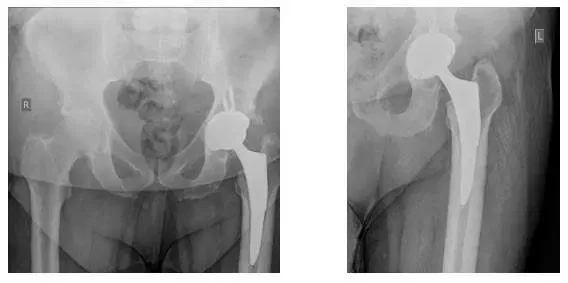

X-Ray of Left Hip during operation. X-Rays show Left Hip Replacement.